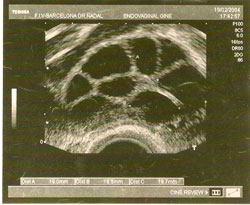

En un proceso de FIV, la mujer debe realizar un tratamiento de estimulación ovárica con medicamentos inductores de la ovulación, cada día más puros y eficaces, para intentar conseguir el máximo número de folículos. Estos tratamientos son siempre personalizados para cada paciente y dependerán de factores como la edad y de los resultados de las analíticas hormonales previas, y supervisados siempre con controles ecográficos y analíticos.

Una vez los folículos alcancen el número y el tamaño idóneo, se administra una nueva medicación para provocar la maduración ovocitaria.